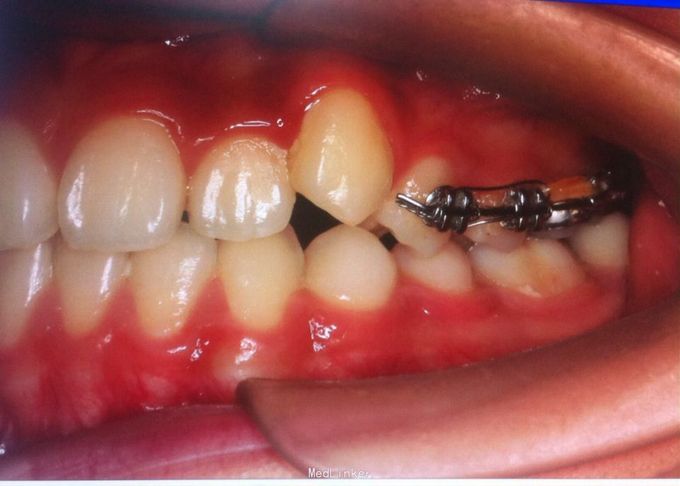

恒牙期 口内见摆式矫治器 左侧磨牙近中关系,右侧中性关系 前牙覆合覆盖正常 中线不正 上下牙列拥挤 张口度正常 关节有弹响 开口型异常

安氏三类 拆除摆式矫治器,清洁牙面,直丝弓矫治器,排齐整平上下牙列,矫治后磨牙中性关系,前牙覆合覆盖正常,维持现有面型